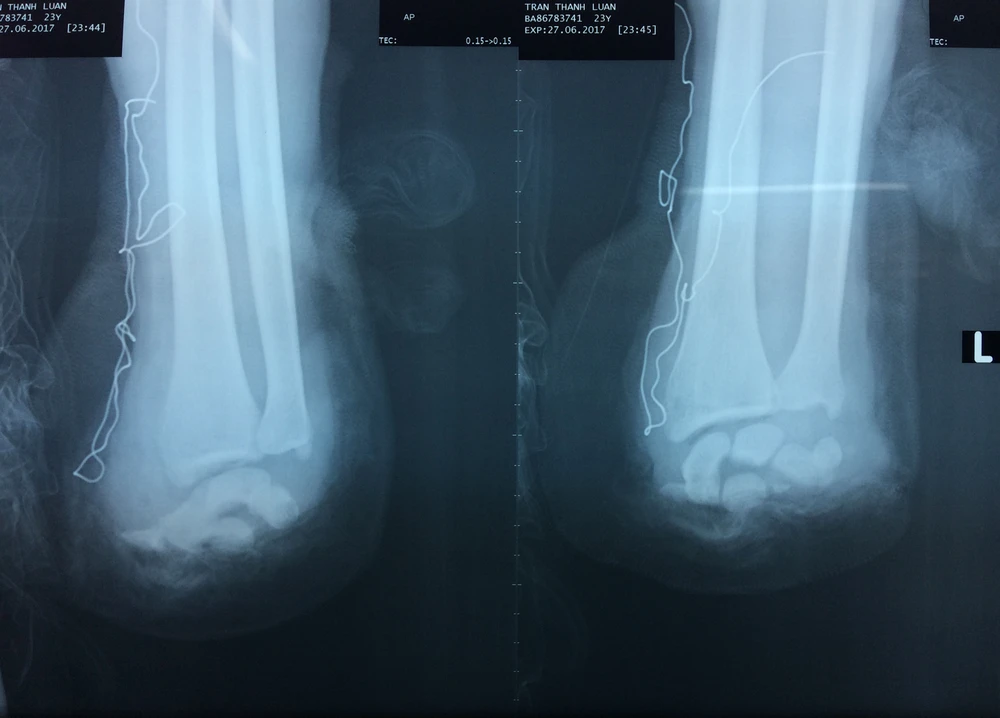

Kết quả chụp X-quang cho thấy bàn tay trái của anh L.bị đứt lìa. Ảnh: HÒA KHÁNH